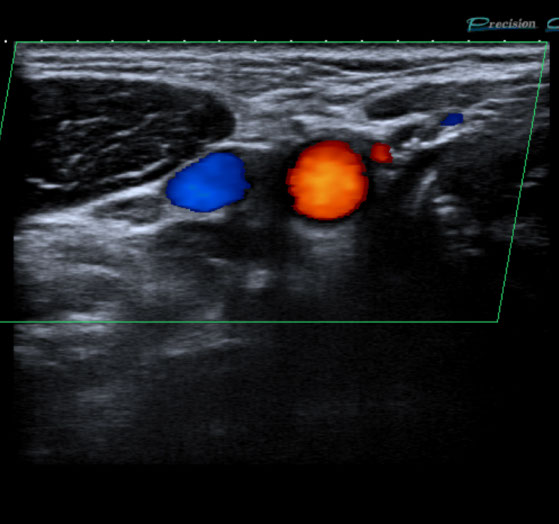

Farbdopplersonographie

Die Farbdopplersonographie ist eine zuverlässige Methode zur Beurteilung von Arterien und Venen. Die Farbdopplersonographie kann einerseits Veränderungen der Gefäßwände (z.B. arteriosklerotische Plaques) und dadurch resultierende Engstellen (Stenosen) nachweisen, andererseits durch Blutflussgeschwindigkeitsmessungen den Schweregrad der Stenosen beurteilen. Risikofaktoren für Arteriosklerose und damit für Schlaganfall und Herzinfarkt sind z.B. erhöhte Blutfettwerte, hoher Blutdruck (Hypertonus), Nikotinkonsum.